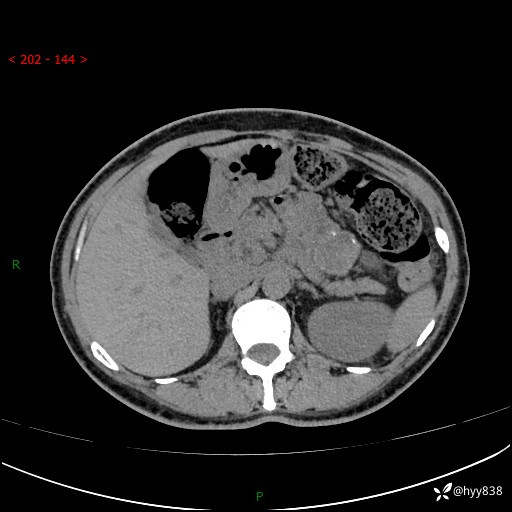

增强动脉期+静脉期

img